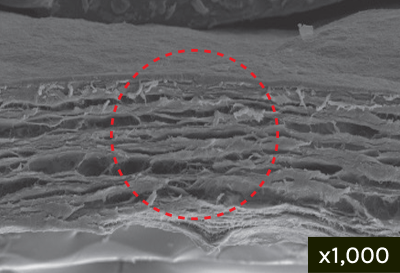

Cross Section

Multi-layer Heterostructure